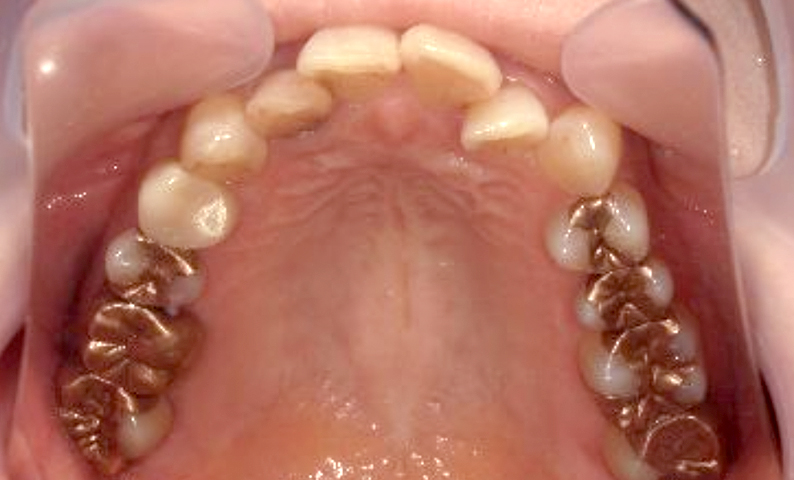

症例_002 上顎だけの部分矯正

治療期間:7ヶ月金額:30万円+税女性前歯のガタガタ上の前歯だけ

| Before | After |

|---|---|

|